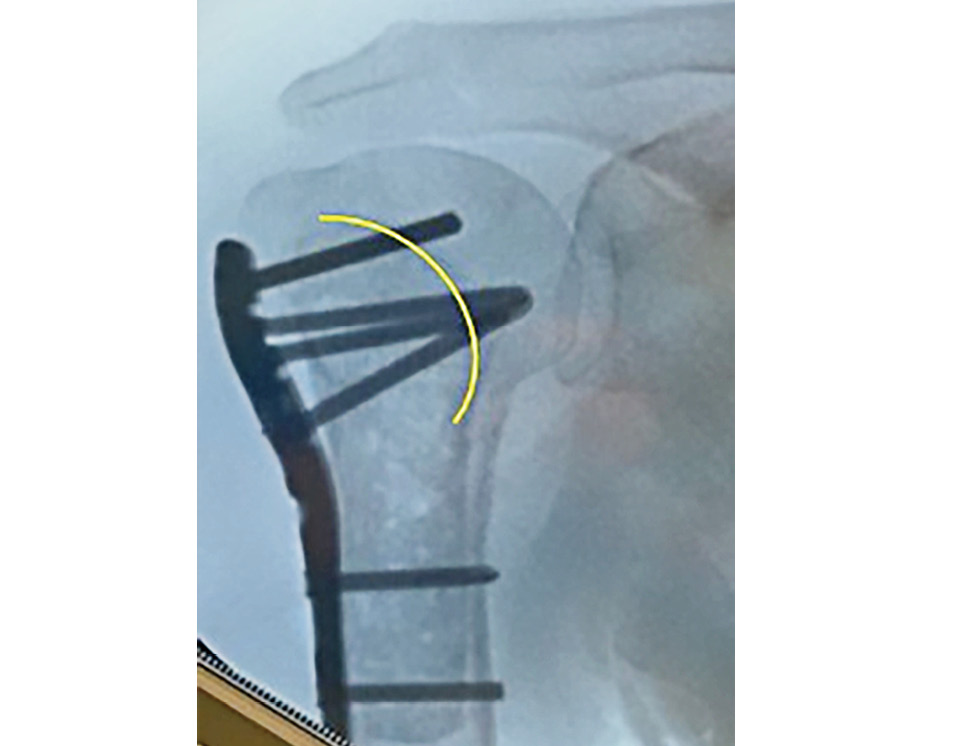

При анализе послеоперационных рентгено- и МСКТ-грамм у всех пациентов отмечено удовлетворительное положение отломков. В 3 (7%) случаях выявлено первичное прорезывание винтов в сустав из-за интраоперационной ошибки хирурга, что потребовало удаления этих винтов. Ошибки обусловлены стремлением использовать максимально длинные винты для того, чтобы «захватить» субкортикальную кость. Стремиться к этому не нужно, поскольку помимо металлической конструкции перелом укрепляет трансплантат, и сухожилия ротаторов плеча подшиты к пластине (рис. 5). Значимого вторичного смещения отломков в послеоперационном периоде ни у кого, кроме 2 наблюдений с отрывом фрагмента большого бугорка, упомянутых ранее, зарегистрировано не было. То есть осложнения развились в 25% наблюдений, а повторные операции (в связи с несращением перелома и по причине прорезывания винтов) были выполнены в 8,33% наблюдений.

Рис. 5. Рекомендуемая длина винтов. Жёлтой линией отмечена граница установленного костного аллотрансплантата.

Fig. 5. Recommended screw length. The yellow line marks the border of the established bone allograft.

В большинстве рекомендаций по остеосинтезу проксимального отдела плечевой кости считается правильной установка винтов до субхондрального слоя головки. Однако при переломах с дефицитом кости в послеоперационном периоде происходит коллапс головки, и установленные таким образом винты выходят в полость плечевого сустава, причиняя пациенту боль. Для профилактики этого осложнения мы стараемся устанавливать как можно более короткие винты, которые на несколько миллиметров выходят за пределы трансплантата. За счёт трансплантата, который служит опорой для суставной поверхности головки плечевой кости, и фиксации нитей от сухожилий вращающей манжеты плеча к пластине создаются достаточные условия для стабильной фиксации, и установки максимально длинных винтов не требуется.